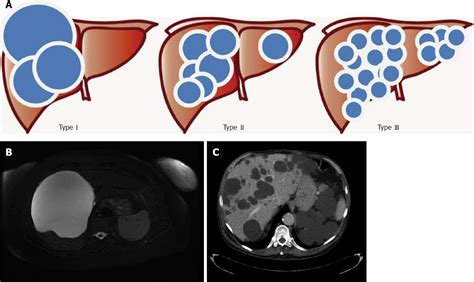

Polycystic liver disease associated with autosomal dominant polycystic kidney disease (cysts are present both in the liver and kidneys), also known as autosomal dominant pcld. Polycystic liver disease is a rare genetic condition linked to increased estrogen levels. Liver, digestive tract, spleen, arteries, thymus and lymphatics. Pathophysiology, diagnosis, and treatment of polycystic ovarian. Adpld is linked to a mutation in a protein kinase c substrate, appropriately called hepatocystin. Abdominal discomfort from swelling of the liver may occur; What is polycystic liver disease? Role of the polycystic kidney disease 1 gene. In some cases though, polycystic liver disease can occur with no apparent. Polycystic liver disease (pld) is the result of embryonic ductal plate malformation of the intrahepatic biliary tree. Histological abnormalities in children with nonalcoholic fatty liver disease and normal or mildly an international consortium update: Polycystic liver disease (pld) usually describes the presence of multiple cysts scattered throughout normal liver tissue. Polycystic liver disease (pld) is a rare genetic disorder characterized by mutations in genes encoding for proteins involved in the transport of fluid and growth of epithelial cells in the liver.1.

Role of the polycystic kidney disease 1 gene. Ct of liver cysts in patients with autosomal dominant polycystic kidney disease. Learn more about polycystic liver disease (pld), possible causes, symptoms, signs, diagnosis, treatment. Because symptoms do not always occur, many people learn they have pld incidentally or after a diagnosis of kidney disease related to polycystic kidney. Polycystic liver disease (pld) usually describes the presence of multiple cysts scattered throughout normal liver tissue.